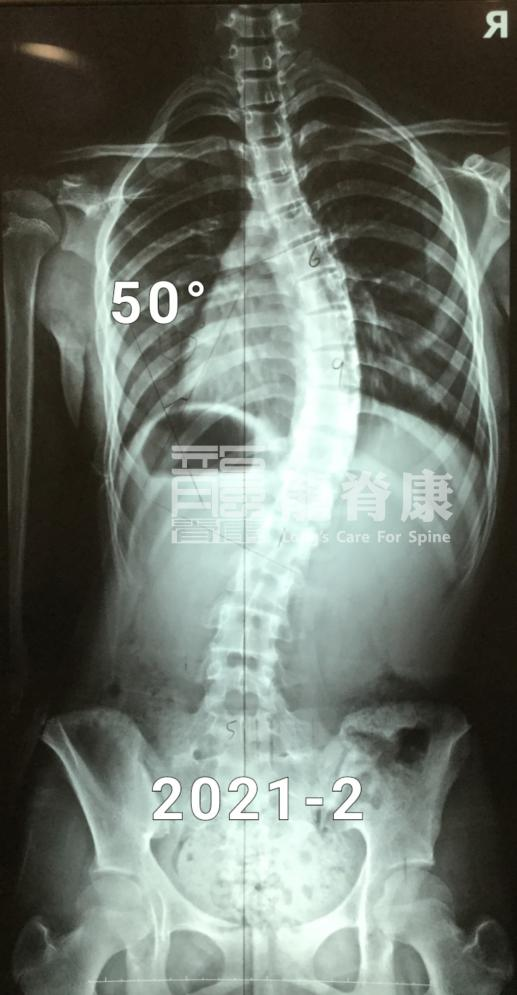

在2021年的春天,13岁的小墨同学和她的父母来到了门诊诊查,原因是2019年的10月份,她在当地医院检查确诊为脊柱侧弯,当时做了一段时间的推拿按摩,但体态问题依然没有改善。

在最初的一年里,小墨坚持每3个月回来复查体态以及调整支具。3个月复查时,脱支具4小时后的X光片显示,她的胸弯度数已经从50°减至39°,且剃刀背都有明显改善,右背部剃刀背由14°减至7°,左腰部剃刀背由12°减至8°。

尽管如此,胸弯角度由50°减少至31°的小墨已经能避免了手术治疗;接下来的时间里,在她骨骼发育基本成熟稳定前,小墨还是需要继续配合治疗以及及时复查,除稳定侧弯减少进展的风险外,她还能为进一步改善体表再努力一把。